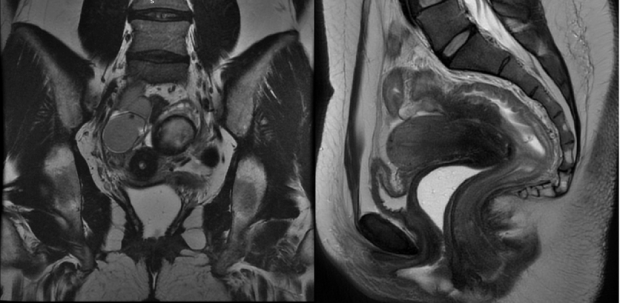

Abaixo vemos 2 ressonâncias magnéticas pélvicas em T2. Na primeira, percebe-se um tecido endometriótico extenso em região posterior ao colo uterino. Na segunda imagem, em uma sequencia sagital, tem-se um tecido endometriótico retrouterino com comprometimento da parede intestinal.